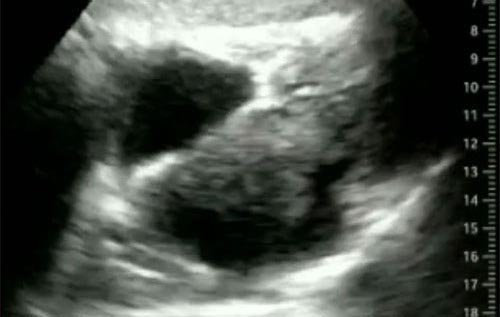

Semana 3

Paciente homem, 68 anos, hipertenso, diabético, sedentário, com infarto agudo do miocárdio há 6 anos. Dá entrada no DE com dispneia. E aí? O que podemos ver nessa imagem?